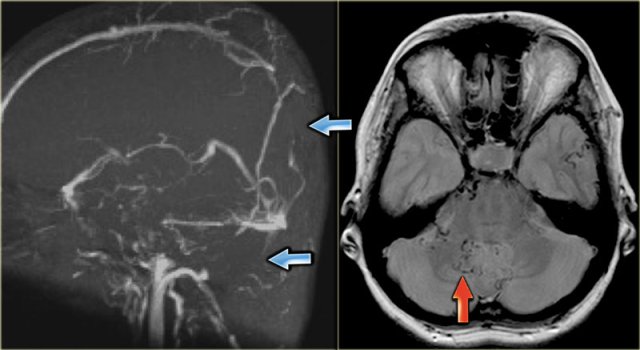

On the left images of a patient with a hemorrhagic infarction in the temporal lobe (red arrow).

Notice the dense transverse sinus due to thrombosis (blue arrows).

On the left images of a patient with hemorrhage in the temporal lobe.

When the hemorrhagic component of the infarction is large, it may look like any other intracerebral hematoma with surrounding vasogenic edema.

The clue to the diagnosis in this case is seen on the contrast enhanced image, which nicely demonstrates the filling defect in the sigmoid sinus (blue arrow).

On the left a similar case on MR.

There is a combination of vasogenic edema (red arrow), cytotoxic edema and hemorrhage (blue arrow).

These findings and the location in the temporal lobe, should make you think of venous infarction due to thrombosis of the vein of Labbe.

The next examination should be a contrast enhanced MR or CT to prove the diagnosis.